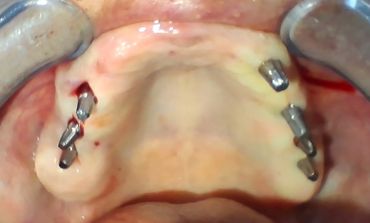

Un implant dentaire est une prothèse fixe utilisée pour remplacer la racine d'une dent manquante. Fabriqué généralement en titane, un matériau biocompatible, l'implant s’intègre naturellement à l’os de la mâchoire grâce à un processus appelé ostéointégration. Une fois l'implant en place, il sert de base solide pour une prothèse dentaire, telle qu'une couronne, un bridge ou une prothèse complète, afin de restaurer à la fois l'esthétique et la fonctionnalité de la dentition.

Voici les principales solutions qui requièrent la pose d’une prothèse dentaire :

Pose d'un implant dentaire